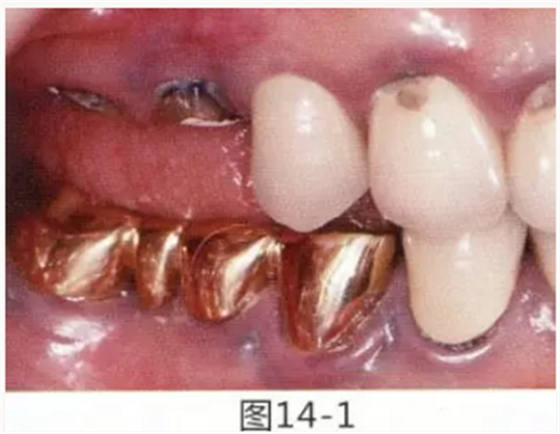

病例5

為了提高對修復(fù)體的術(shù)后效果,以生物學(xué)寬度,獲取附著齦為目的進行游離齦移植的病例

圖14-1 修復(fù)體周圍角化牙齦較少,很難進行清潔的狀態(tài),并有緣下齲壞的發(fā)生。

圖14-2,3 徹底去除齲壞后,試圖通過游離齦移植獲取生物學(xué)寬度和附著齦。

圖14-4~6修復(fù)體周圍角化牙齦較少,很難進行清潔的狀態(tài),并有緣下齲壞的發(fā)生。

圖14-7 配戴最終修復(fù)體完成5年后的狀態(tài)。保持良好。